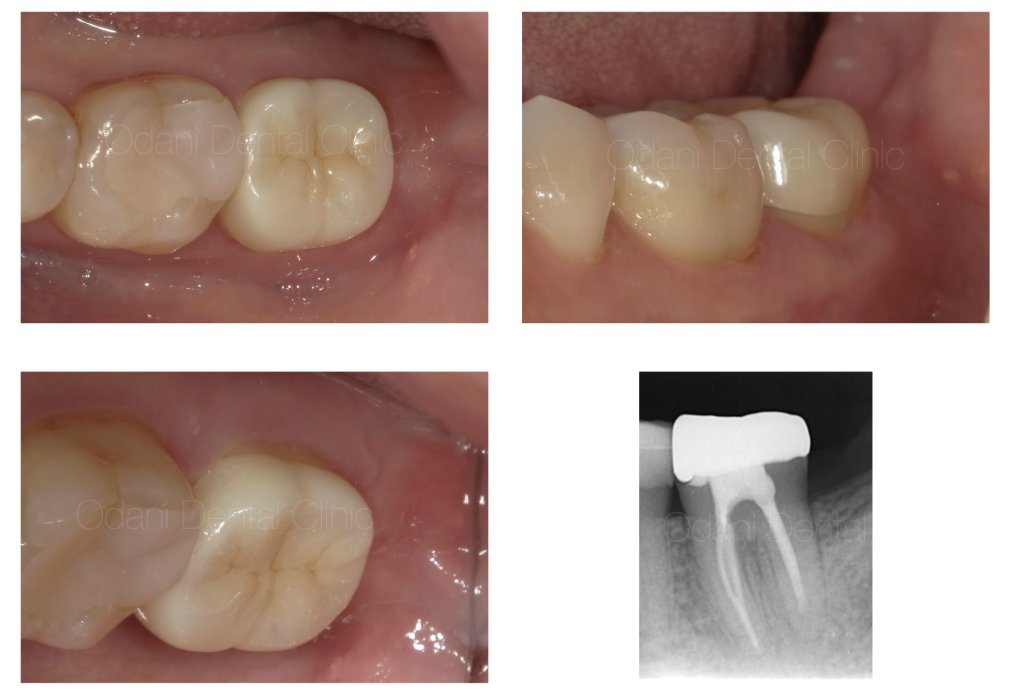

治療終了時の状態

根管治療後、 術後3ヶ月な状態です。黒い影がなくなり、骨が回復している様子が伺えます。

痛みや腫れ等の症状も全てなくなったため、最終のかぶせ物の治療を行いました。

- 治療期間:根管治療後、約3か月経過観察を行い、CT画像にて治癒が確認できたため、最終的なかぶせ物の治療へ移行しました。